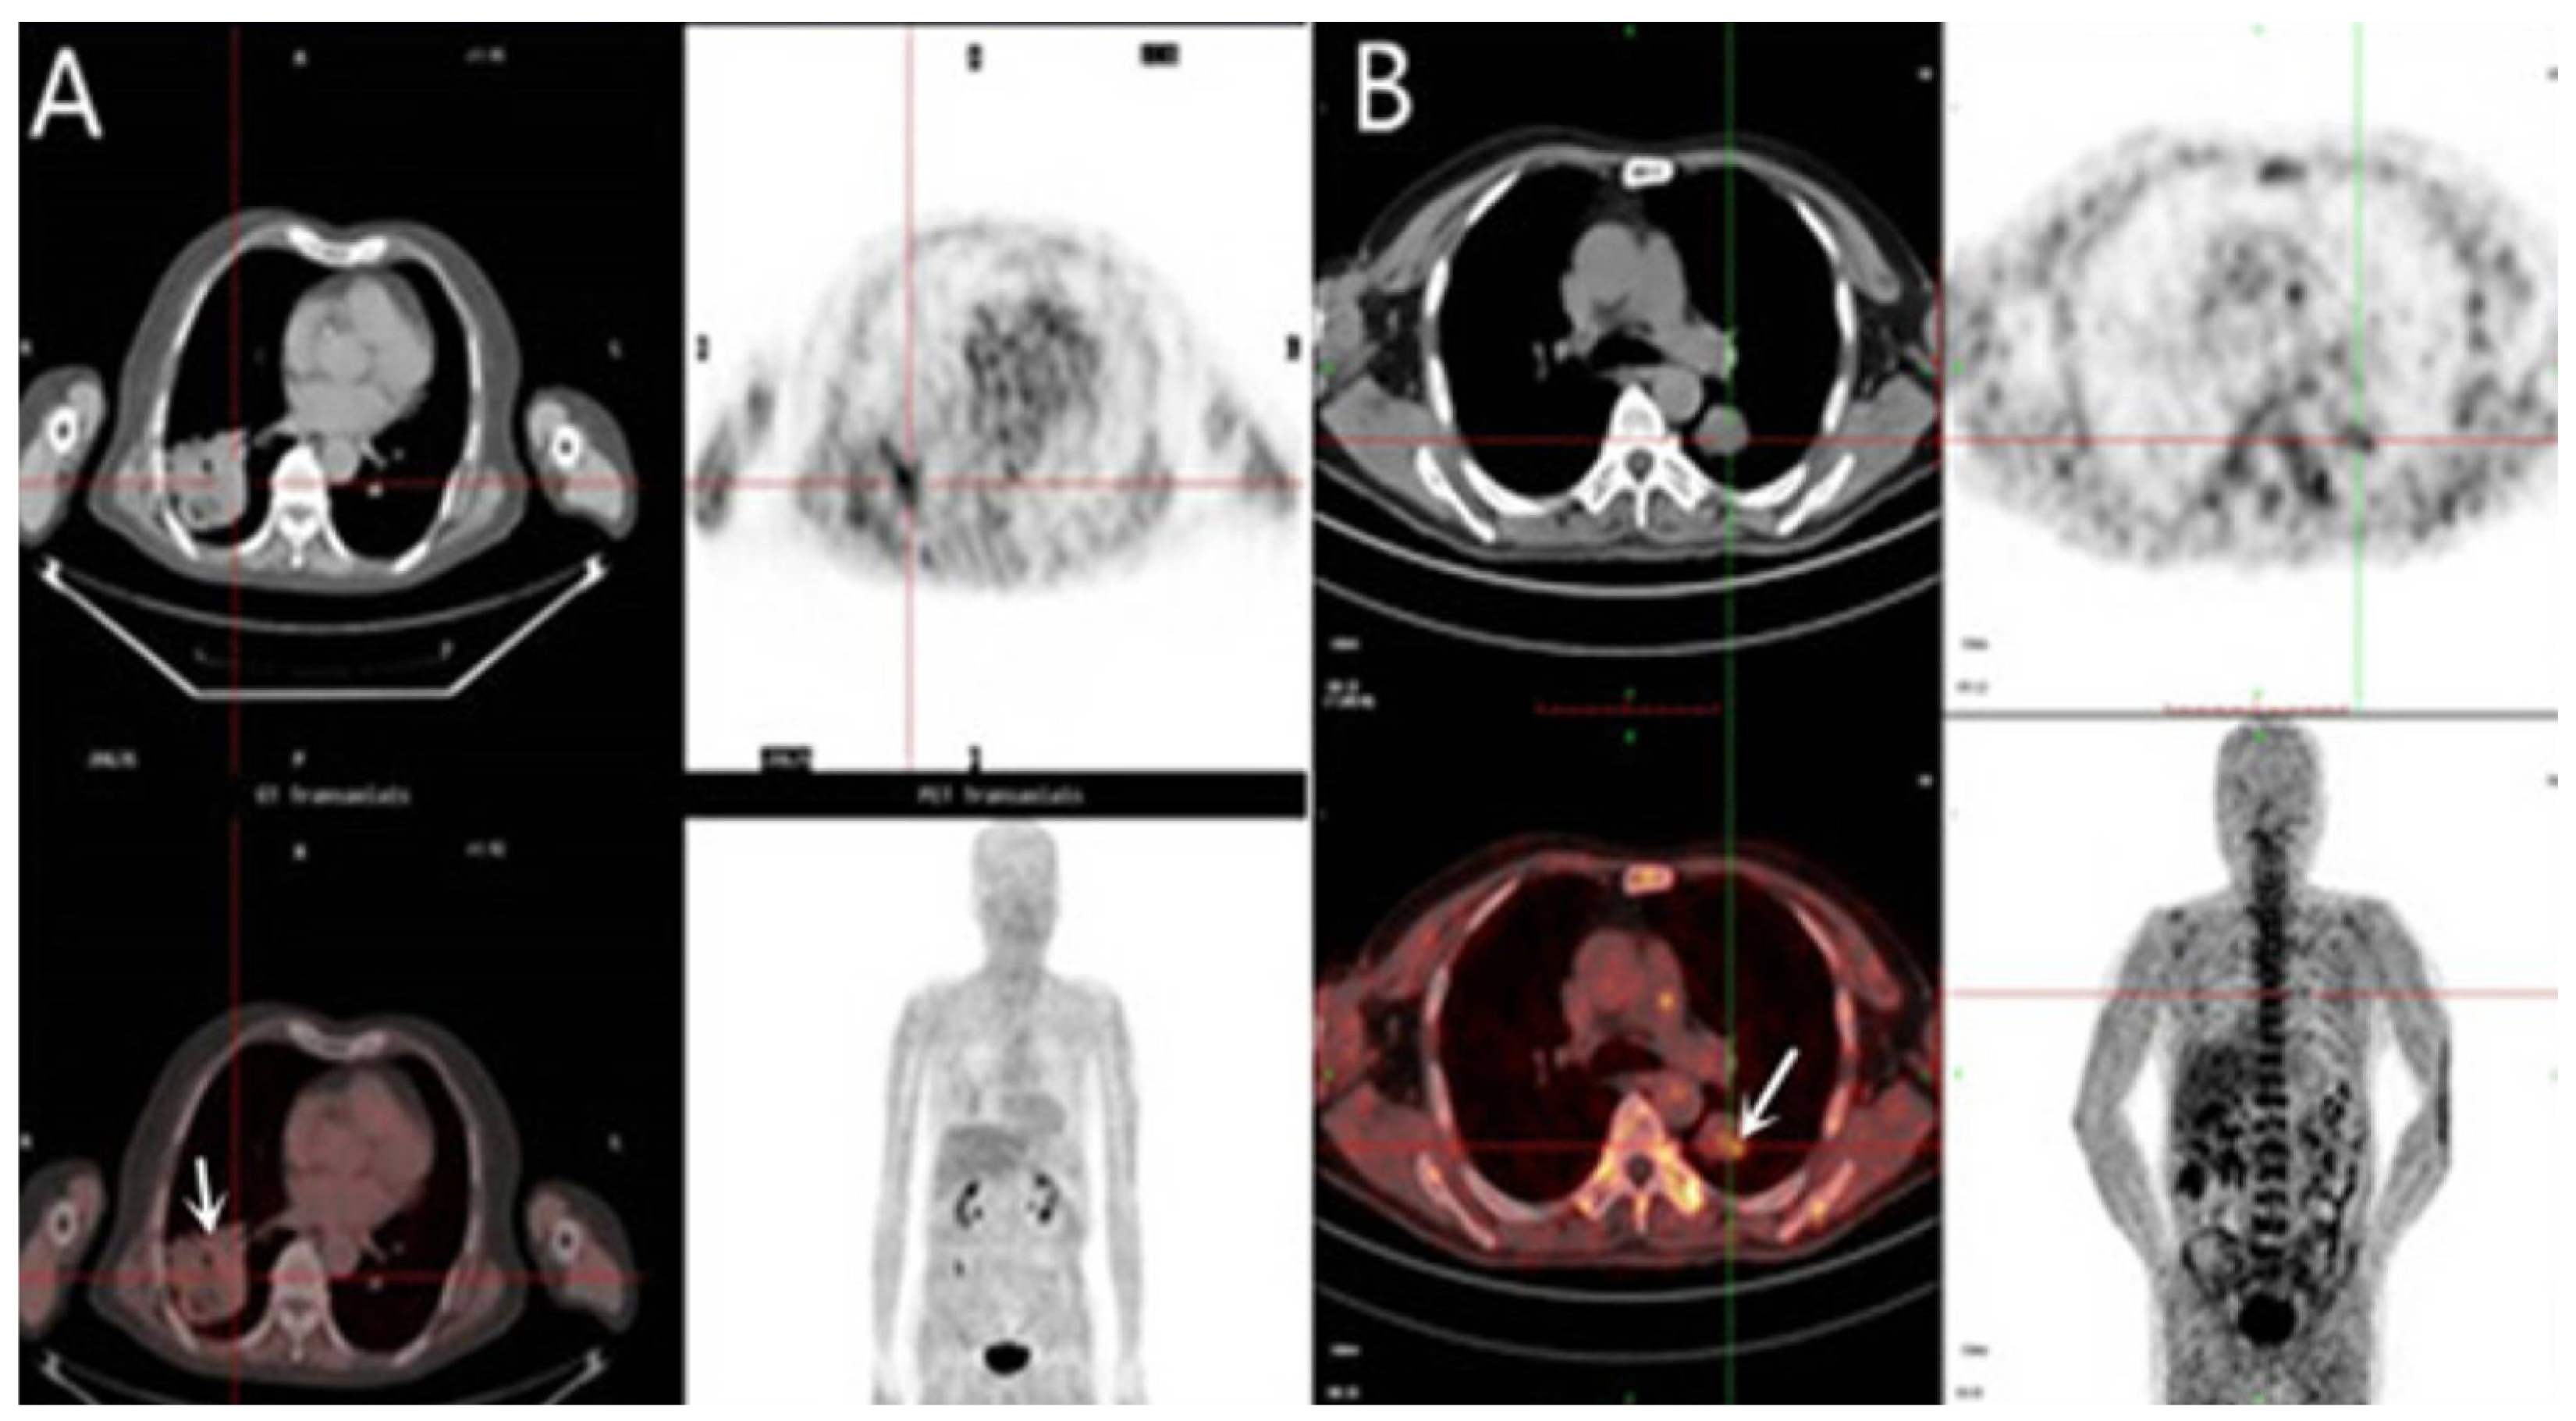

- Watanabe, S.; Inoue, T.; Okamoto, S.; Magota, K.; Takayanagi, A.; Sakakibara-Konishi, J.; Katoh, N.; Hirata, K.; Manabe, O.; Toyonaga, T.; et al. Combination of FDG-PET and FMISO-PET as a treatment strategy for patients undergoing early-stage NSCLC stereotactic radiotherapy. EJNMMI Res. 2019, 9, 104. [Google Scholar] [CrossRef]